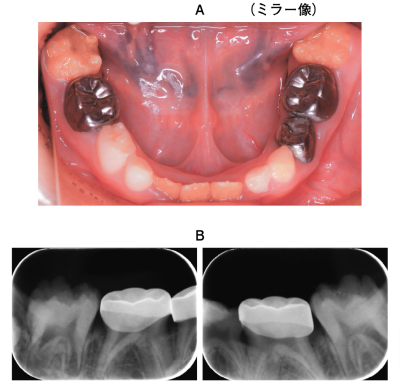

6歳の女児。下顎両側第一大臼歯の冷水痛を主訴として来院した。萌出時から歯の形成不全が認められたという。初診時の口腔内写真エックス線画像を別に示す。

保護者への説明で適切なのはどれか。1つ選べ。